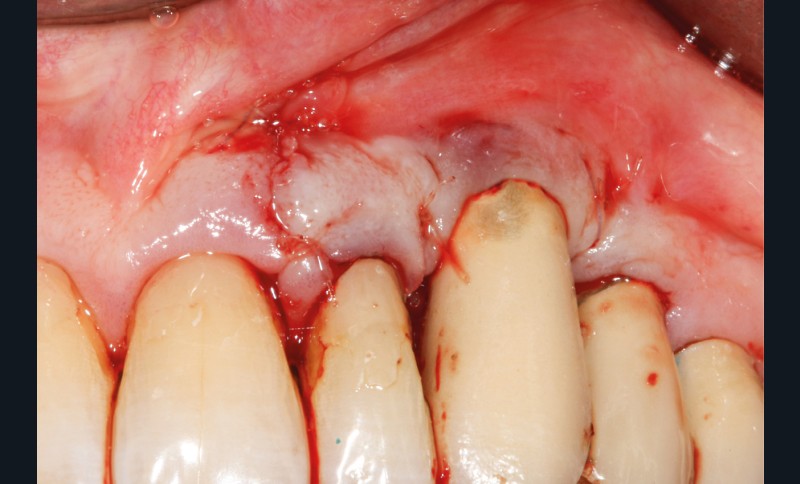

Le patient

- 70 ans

- Pas d’antécédents médicaux

- Ne fume pas

- Hygiène correcte

L’implant

- Site 23

- Mis en place il y a 12 ans